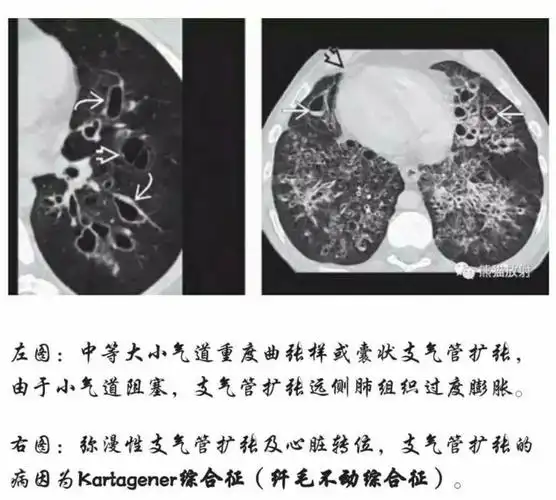

ct支扩的表现